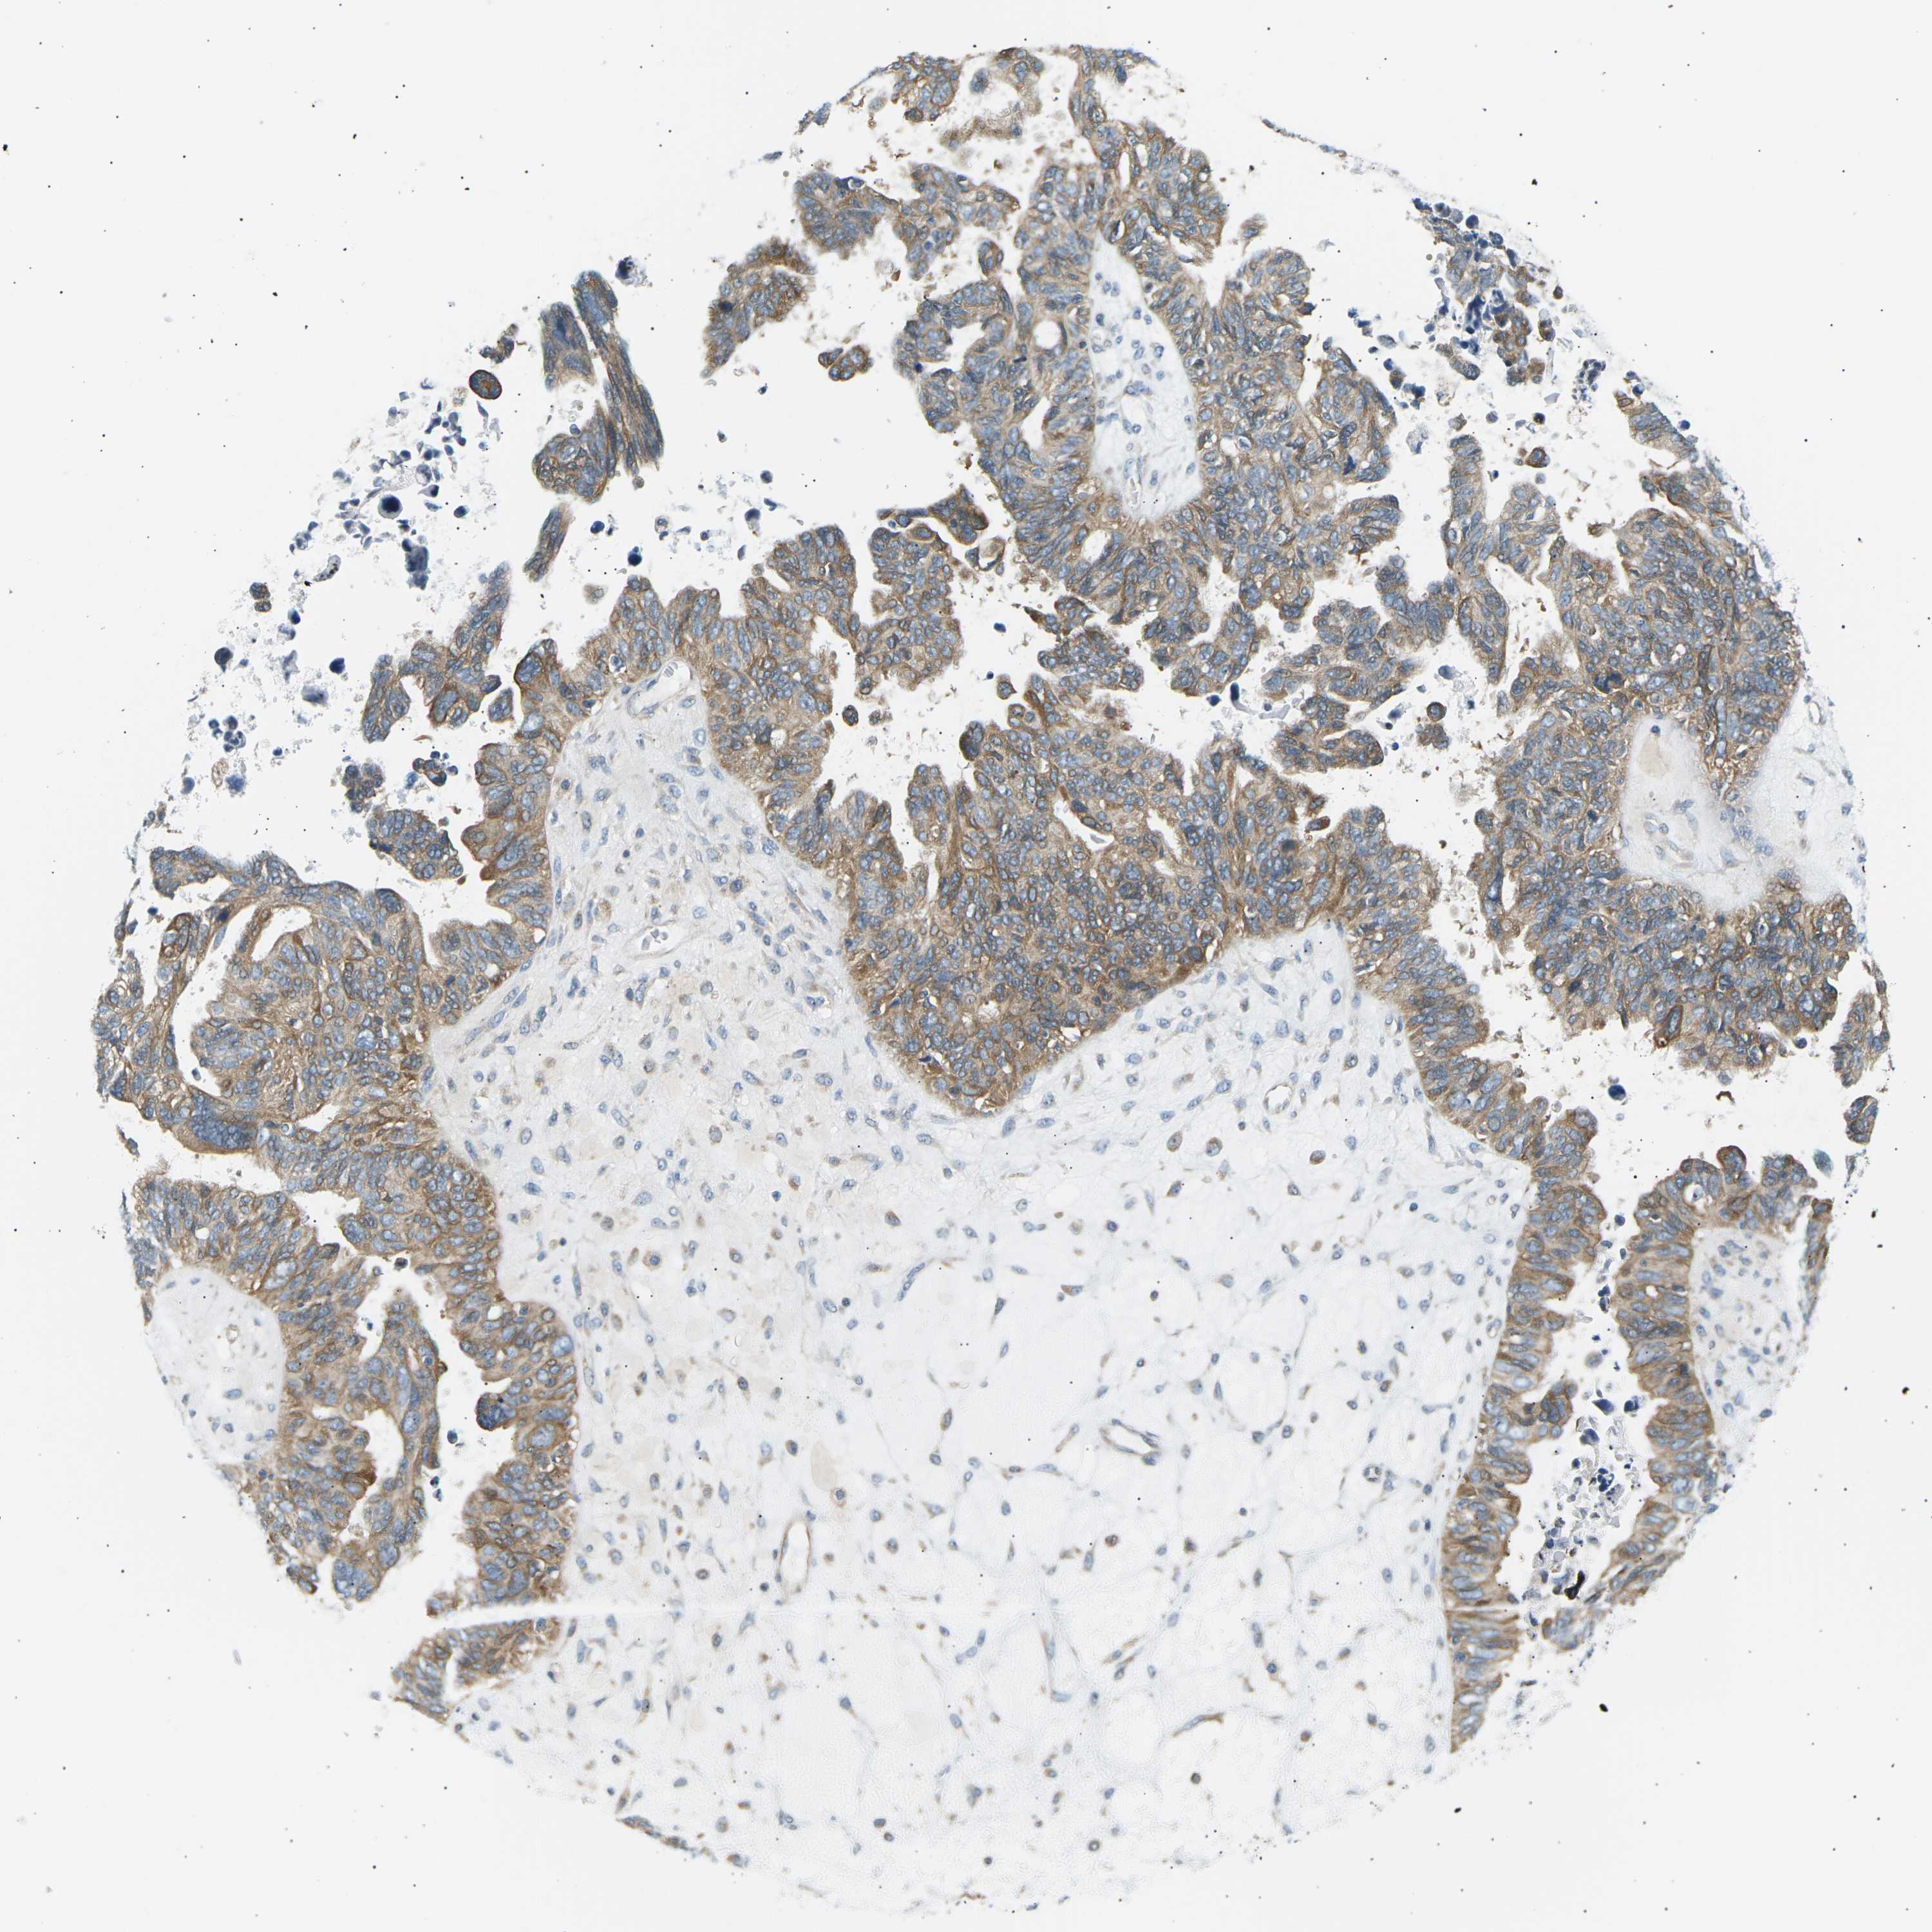

OVARIAN CANCER - Protein expressioni

A mouse-over function shows sample information and annotation data. Click on an image to view it in a full screen mode. Samples can be filtered based on level of antibody staining by selecting one or several of the following categories: high, medium, low and not detected. The assay and annotation is described here.

Note that samples used for immunohistochemistry by the Human Protein Atlas do not correspond to samples in the TCGA dataset.

Antibody stainingi

Antibody staining in the annotated cell types in the current human tissue is reported as not detected, low, medium, or high, based on conventional immunohistochemistry profiling in selected tissues. This score is based on the combination of the staining intensity and fraction of stained cells.

Each image is clickable and will lead to virtual microscopy that enables deeper exploration of all samples and also displays staining intensity scores, fraction scores and subcellular localization as well as patient and tissue information for each sample.

Antibody CAB015211

Cystadenocarcinoma, serous, NOS

Carcinoma, endometroid

Cystadenocarcinoma, mucinous, NOS

Carcinoma, NOS